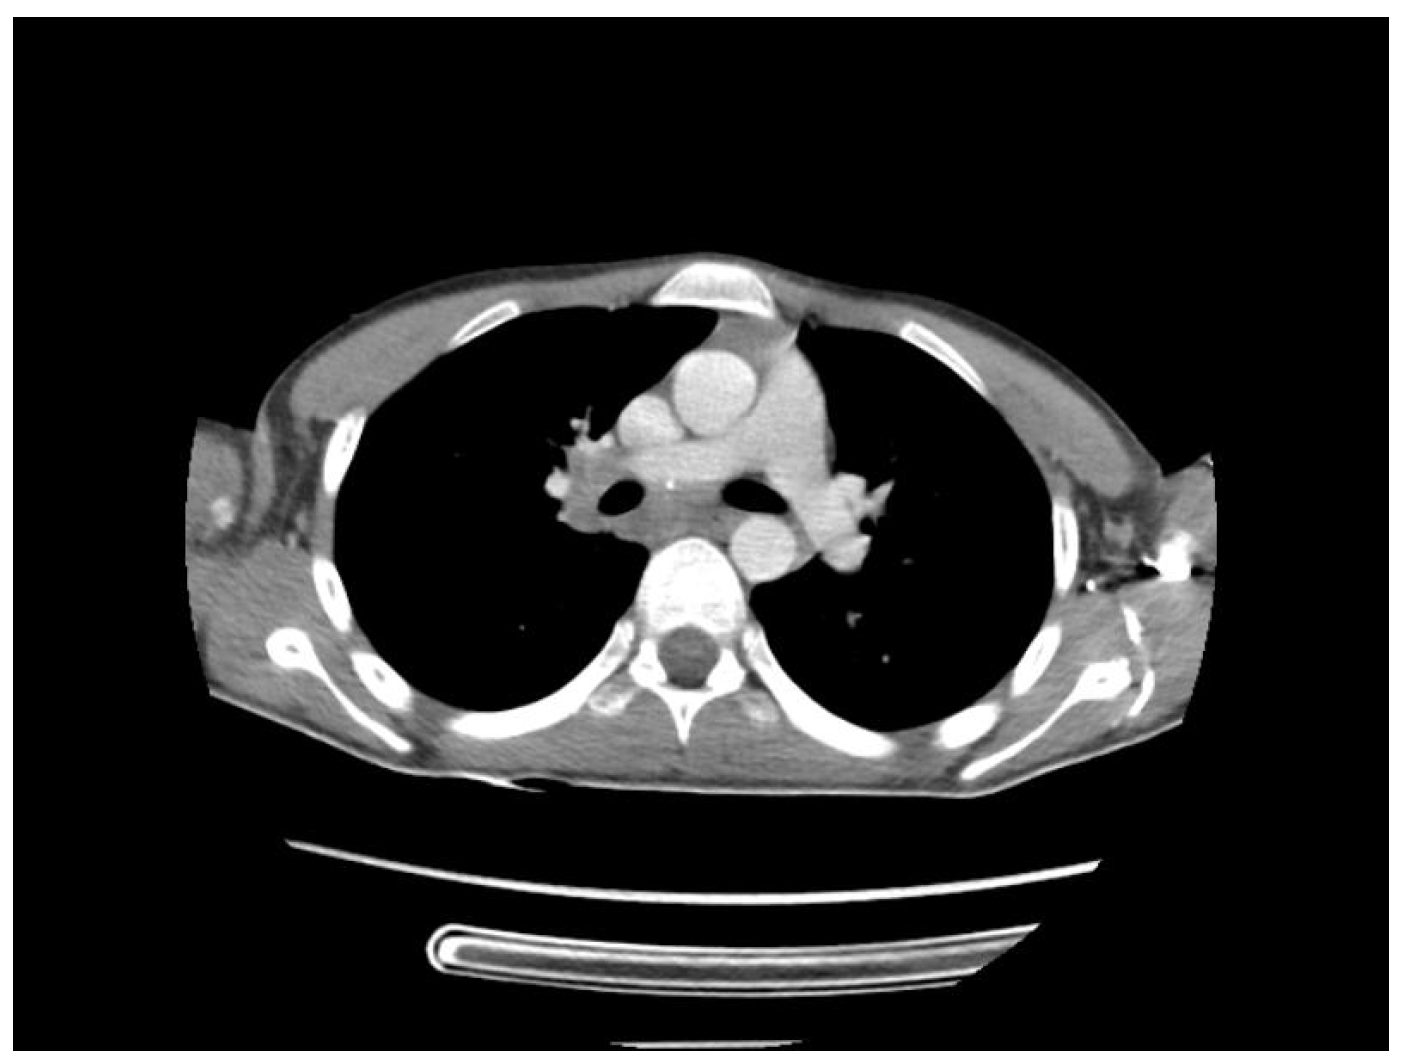

2. Case Presentation